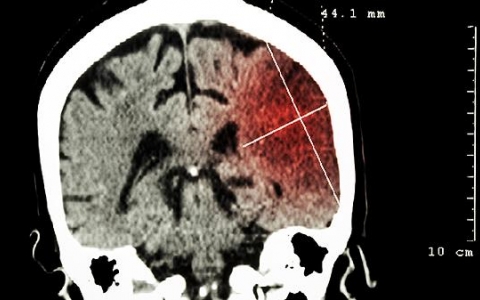

慢性脑梗死的情况是什么?

慢性脑梗死的情况是什么?慢性脑梗死多指缺血性中风,主要由颅内或颈部动脉粥样硬化引起,常引起肢体麻木、视觉变化、口齿不清等。缺血性中风是指颅内或颈部动脉粥样硬化等

脑梗死的七个前兆症状

脑梗死的前兆症状:脑梗死没有7个前兆,有的患者会出现嘴角歪斜、言语不良、一侧肢体无力或麻木、意识障碍、癫痫等症状。要注意识别,千万不要错过治疗机会,造成严重后果